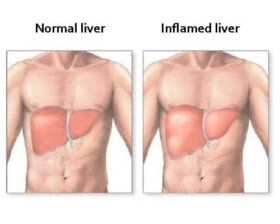

간에 염증이 생겼는가? 이 글에서는 간 염증을 알려주는 몸의 신호들을 소개하고 이에 대한 치료법과 예방법을 알려줄 것이다. 간 염증을 알려주는…